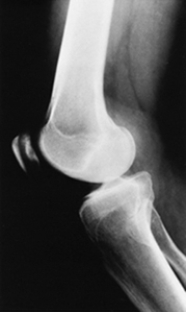

Which of the following imaging techniques illustrated in the pictures would be the most efficient to discover if there is a nerve root compression at the L4 level?

Q16: Which of the following imaging techniques illustrated

Q17: Which of the following imaging techniques illustrated